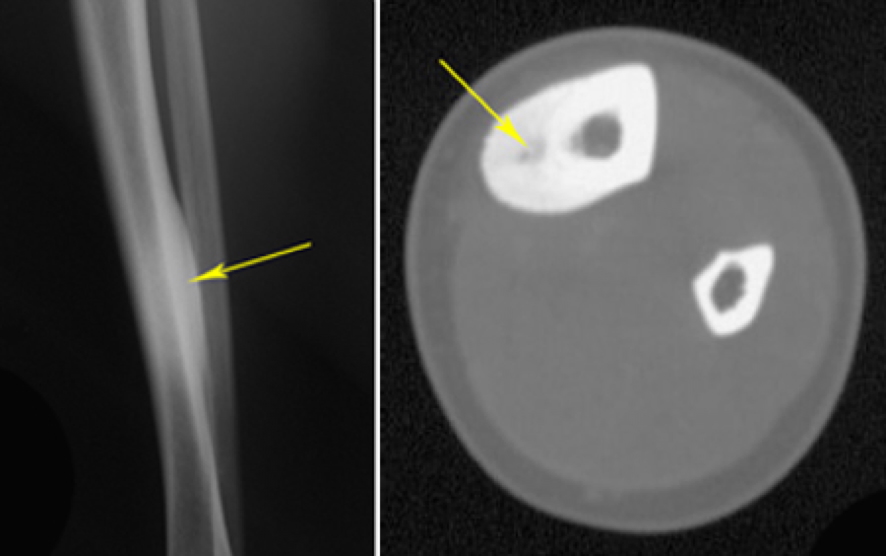

- X-ray and CT scan:

- Small, round radiolucent nidus with surrounding sclerosis

- Usually <1.5 cm diameter